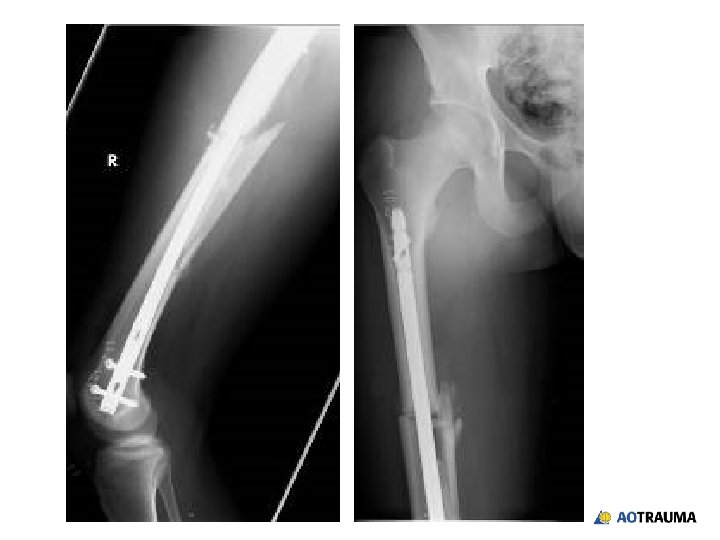

19 -year-old in a motorcycle accident • Injury to right femur • Closed •

19 -year-old in a motorcycle accident • Injury to right femur • Closed • Neurovascular structures intact • Stable vital signs

Your treatment of choice is: 1. Piriformis entry, antegrade nail 2. Trochanteric entry, antegrade

Your treatment of choice is: 1. Piriformis entry, antegrade nail 2. Trochanteric entry, antegrade nail 3. Retrograde nail 4. Plate